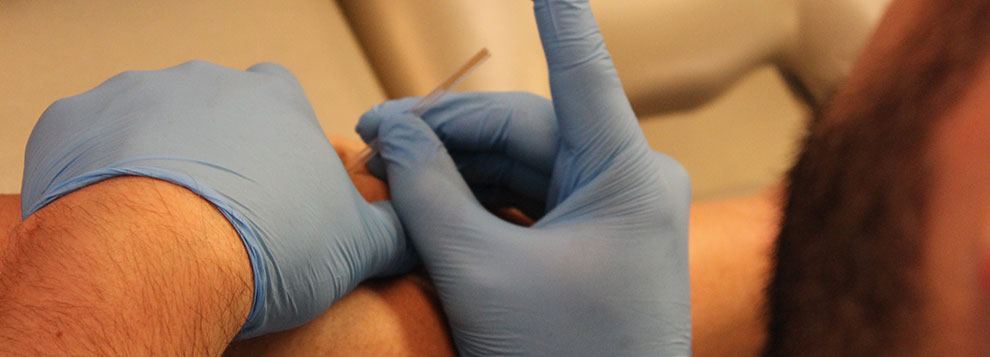

The diagnosis of peroneal tendonitis is usually made by examination of the ankle. The physical examination helps determine where the tendons are inflamed, ruptured, or degenerated. Your physical therapist at Iron City Physical Therapy will move your ankle into different positions, checking the peroneal tendons by holding your foot up and out against the therapists downward pressure. Stretching the foot up and in can also be used test whether the tendons hurt.

In rare cases, cortisone can be injected into the sore tendons to relieve symptoms that won't go away. Cortisone is a powerful anti-inflammatory medication. Because there is a risk that cortisone will cause a tendon to rupture, doctors are very cautious about injecting cortisone into the peroneal tendons.